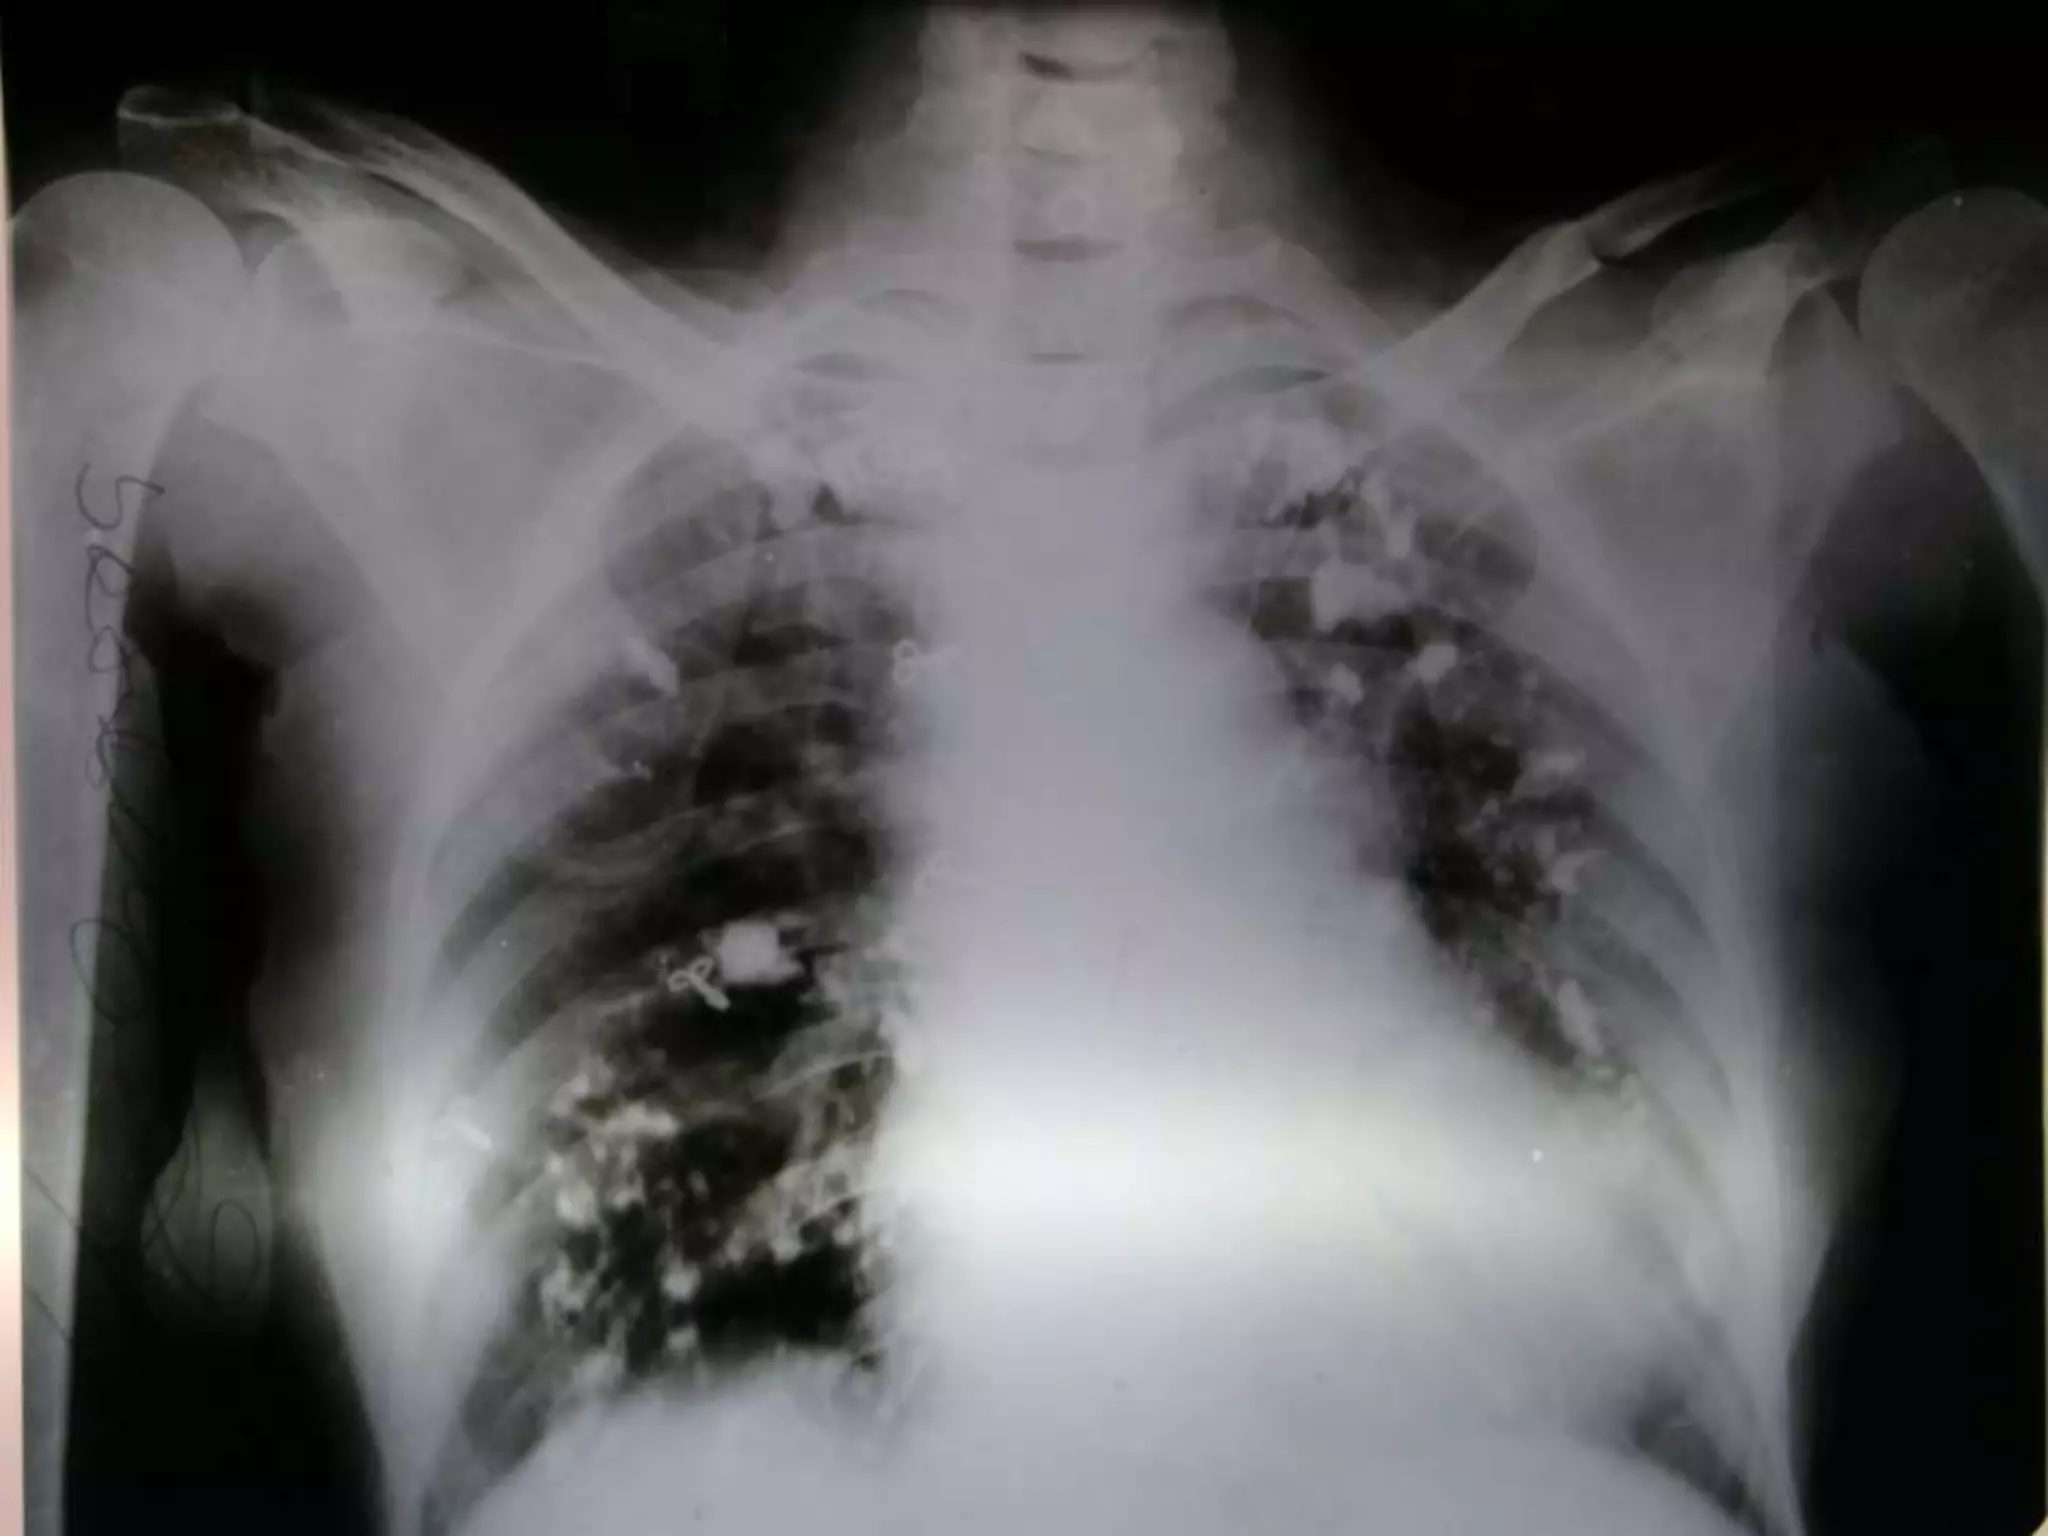

The chest x-ray shows multiple, irregular, dense opacities diffusely over the lung fields, which are indicative of pleural calcification or pulmonary parenchymal calcification. The differential diagnoses for pleural calcification include healed hemothorax/pyothorax, tuberculous effusion, and pneumoconioses. The differential diagnoses for parenchymal calcification include tuberculosis, histoplasmosis, solitary pulmonary nodules, silicosis/talcosis, tuberculosis/histoplasma/varicella, sarcoidosis/amyloidosis, and metastatic disease in the case of dendriform patterns. The cardiomediastinal and bone soft tissue shadows appear